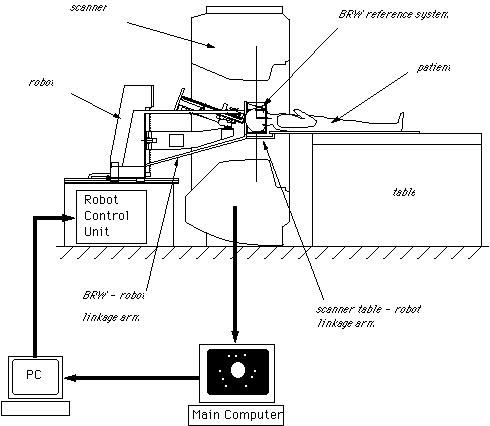

There are two important stages in the registration procedure - fixation of the patient and the robot, and intra-surgical registration itself.

Fixation is an essential ingredient of a successful robotic operation. Robots act upon pre-programmed paths (as mentioned above), these programs are much more complex (and more difficult to prove for safety aspects) if they must take into account the fact that the patient's position may be different to the inputted data and, in fact, continually changing. For this reason it is imperative that the robot can act in, at least, a semi-ordered environment. Fixation of the patient, that is fixing the patient in position (i.e. on the operating table), is achieved through strapping and clamping of the areas pertinent to the surgery. This is common in traditional surgery, too. For example, the leg of a patient undergoing a knee operation is clamped in position to avoid unintentional movement; similarly, the head is fixed in position during neurosurgery through the application of a head-fixation device known as a 'stereotactic unit'. Fixation of the robot is achieved through analogous methods. Patient held in fixed position for neurosurgery The intra-surgical registration itself is the process of establishing a common reference frame between the pre-surgical data (3D model and associated surgical plan) and the corresponding patient anatomy. Once a common reference is established, pre-surgical data can be safely used to guide robotic movements.There are two primary techniques of achieving this common frame of reference. The first, and most usual, method is to attach fiducials (physically implanted markers) to the underlying patient structures pre- operatively (and necessarily before imaging takes place). These fiducials are then sensed, and compared to the pre-operative data, to precisely align the two data sets. Unfortunately, this 'fiducial- based' registration typically requires an additional surgical operation in itself, in order to attach the markers. Furthermore, these fiducials are invasive and cause added trauma to the patient in sites physically far from the primary field of surgical focus. The alternative to fiducial-based registration is that of 'surface- based' registration. This technique uses surfaces that are intrinsic to the data itself. If surfaces can be extracted from both the pre- and intra-surgical data, then these data sets can be matched to perform registration. The benefit of this method is that it does not require the use of expensive and traumatically invasive markers. The success of surface-registration is highly dependent upon the realism and accuracy of the 3D models gained pre-operatively and upon the sensing accuracy of intra-surgical data acquisition. Geometric surface model validation is complicated since errors can be introduced at several stages of model creation: during imaging, 'segmentation' (seperation of different tissues within a medical image), and surface creation. Prior to the emergence of surface-based techniques for surgery, 3D modelling of medical data has been primarily used as a teaching aid in the study of anatomy (e.g. VOXEL-MAN). These models have very different accuracy requirements to those used for surface-based registration. For instance, the ease with which an object of interest (e.g. a particular organ) can be segmented from surrounding objects is of crucial importance in robotic surgery since any 'blurring' of edges could mean that erroneous incisions are made. Another demand, placed upon the geometric model of the patient, is the ability to cope with 'spatial density' variation within an object. Density variations, like those in real bones and tissue, complicate segmentation by reducing the effectiveness of simple thresholding schemes (methods that interpolate a density from the surrounding data and assign the density value according to certain, pre-determined, thresholds).

The robots used for automated surgery tend, at the present time, to be adapted industrial robots; for example, the PUMA robot arm. The reasons behind this are predominantly financial ones. Investing in the research and development of a robot for a specific task is highly expensive - costs running into millions of pounds, with no guarantee that a suitable product will be the outcome. Another hurdle is the lack of official safety guidelines and standards. Having brought up the fact that the surgeon is reliant upon the engineering behind the tools that they are using, it is clear that companies would not wish to risk possible legal proceedings should one of their products fail. (These issues will be further discussed in the section on safety). As it stands, industrial robots are adequate for the tasks involved, although it is hoped (and expected) that, in the future, surgery- specific robots will be developed and will become an industry of their own. Once the robotic procedure is initiated, sensors collect real-time data from the operating site and pass this to a display, via which the surgeon observes the operation. The type of sensor that seems to best suit the surgical application is the use of infra-red transmitters on the robot's 'joints', that are detected by cameras in the operating theatre (currently under commercial development by General Electric). From these, the exact position of the robot's appendages can be gauged and relayed back to the surgeon's display. It is an issue as to what control a surgeon should have when overseeing an automated surgery - as they may do more damage than good if they intervene. The most common arrangement is to have a 'stop' switch and perhaps a 'redo' control. Sensing the patient, intra-surgically, is fairly simple when using fiducials (the fiducials are specially made from materials that are easily detectable under the system being used). This is not the case, however, when using the preferred surface techniques. Here a variety of systems are under consideration, including an ultrasound sensor or an x-ray sensor - both mounted on a 'C-arm' so that they can move around the whole area of the patient. |